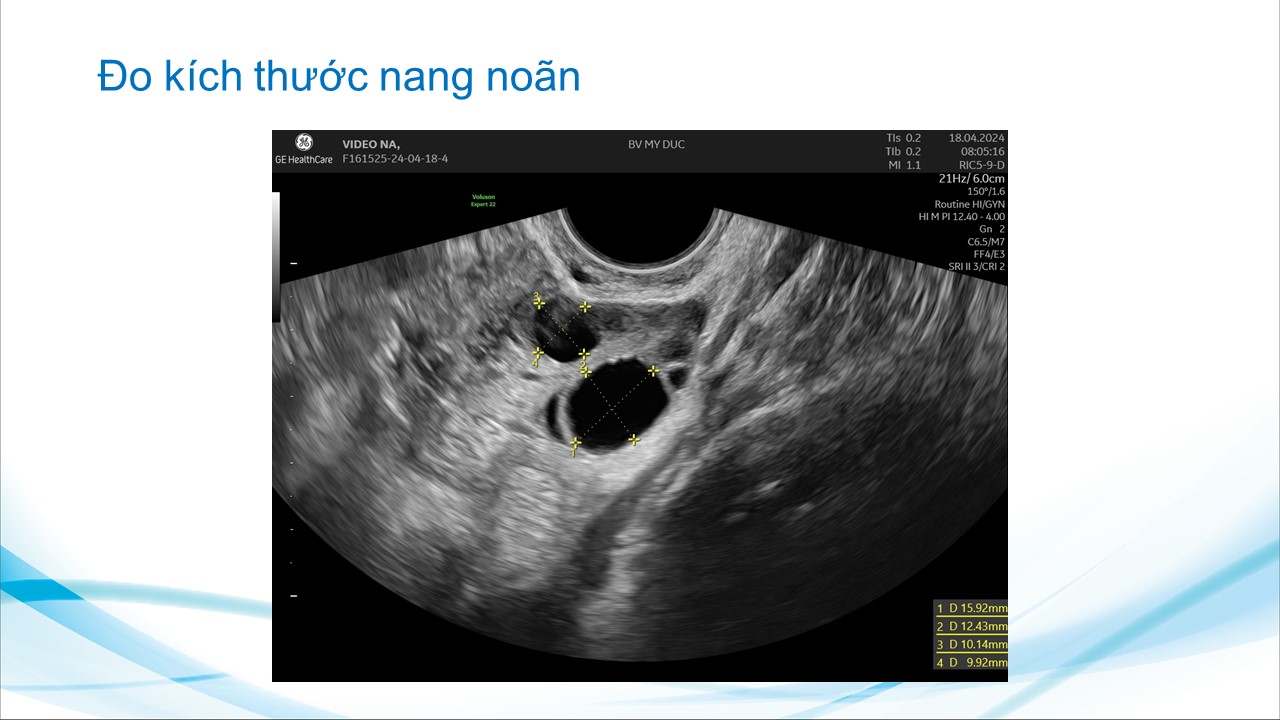

Siêu âm theo dõi trong bơm tinh trùng vào buồng tử cung và thụ tình trong ống nghiệm